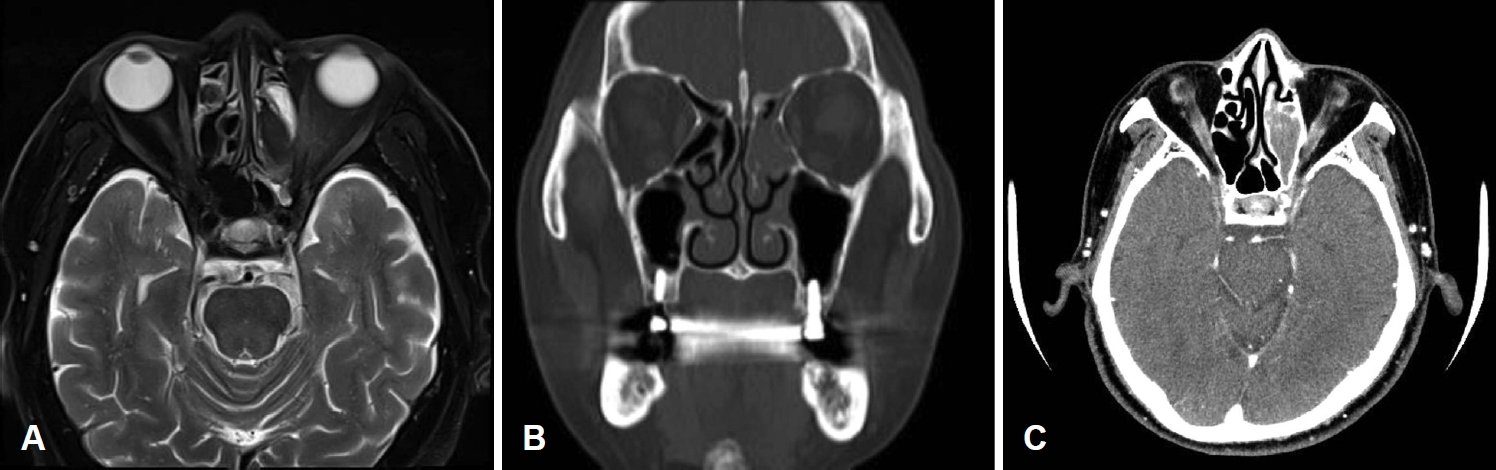

CaseA 69-years-old male visited to the department of ophthalmology, university hospital with complaining left visual disturbance and orbital swelling. He had no symptom associated to nose such as nasal obstruction, rhinorrhea or anosmia. The family histories and past histories were negative for significant disorders. The patient checked fundus photography, visual field exam and oribit MRI in the out patient department of ophthalmology. Orbit MRI showed left ethmoid fungal sinusitis with optic neuritis, the patient was transferred to otorhinolaryngology department. Paranasal sinus (PNS) CT with thin section enhanced and laboratory examination were checked. PNS CT showed left ethmoid fungal sinusitis with mild enhancing left cavernous sinus. On sinus endoscopic examination, we could find mucoid rhinorrhea drained from left osteo-meatus unit site. We prepared for an emergency endoscopic sinus surgery (Fig. 1).

NotesAuthor Contribution Conceptualization: Jun-Won Seo, Ji Yun Cho. Data curation: all authors. Formal analysis: all authors. Investigation: all authors. Methodology: Jun-Won Seo, Ji Yun Cho. Project administration: Ji Yun Cho. Resources: Jun-Won Seo, Ji Yun Cho. Software: all authors. Supervision: Ji Yun Cho. Validation: all authors. Visualization: Do Yoon Jeong, Hyejeen Kim. Writing—original draft: all authors. Writing—review & editing: Ji Yun Cho. Fig. 1.Radiology findings. A: Axial view of orbit MRI showed T2 low signal intensity lesion in the left ethmoid sinus, mild engorgement of left cavernous sinus and mild enhancement of left orbit. B: Axial view of enhanced PNS CT showed inhomogeneous enhancement with mucosa thickening in left ethmoid sinus with calcifications and mild enhancing left cavernous sinus. C: Coronal view of non-enhanced PNS CT showed soft tissue density filled in the left ethmoid sinus with calcifications. PNS, paranasal sinus. Fig. 2.Visual field examinations. A: Preoperative visual field exam showed left visual disturbance as low visual field index (VFI: 12%). B: Postoperative visual field exam showed improved left visual disturbance as increased visual field index (VFI: 43%). VFI, visual field index. REFERENCES1. Holroyd KB, Manzano GS, Levy M. Update on neuromyelitis optica spectrum disorder. Curr Opin Ophthalmol 2020;31(6):462-8.